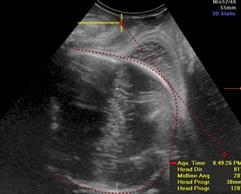

GE公司的SonoVCAD labor技术是基于三维容积超声的计算机辅助产程监测软件。利用三维超声多平面成像技术,可同时显示相交平面,增加了更多信息,使得测量的切面更为准确,重复性佳[5]。软件可在三维容积数据的不同平面自动测量出相应的胎头方向角(图1)、胎头进展角(图2)、胎头下降距离(图3)及中线角(图4)这四个参数,并在产程中动态观察各参数的变化,利用软件记录产程的全过程(图5),从而监测第二产程进展。

图1.在 A 平面, 描记胎头最大经线,从胎头中间点向外拉线,十字交叉点落在胎头轮廓的最远点,并与胎头最大经线垂直。胎头方向角就是耻骨联合下缘垂线和与胎儿颅脑最宽径的垂直线的夹角。